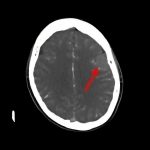

断層撮影

手術前1

手術前2